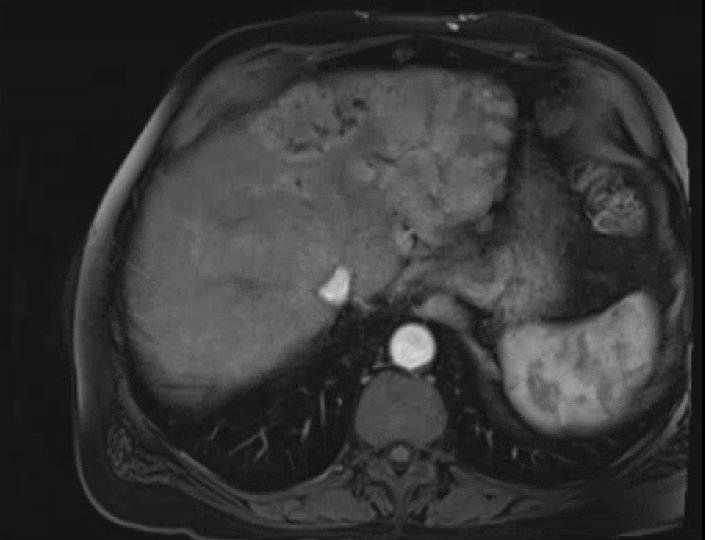

• 74 y. o. male with a large left lobe HCC involving Segment

• 74 y. o. male with a large left lobe HCC involving Segment II, III, and IV also with left portal vein thrombosis. Biopsy confirmed at OSH as moderately differentiated HCC. BCLC stage C tumor. Child-Pugh A with an ECOG PS of 0. Patient presented to MGH for consideration of radioembolization. Patient did not desire chemotherapy due to significant side-effects

Pre-SIRT